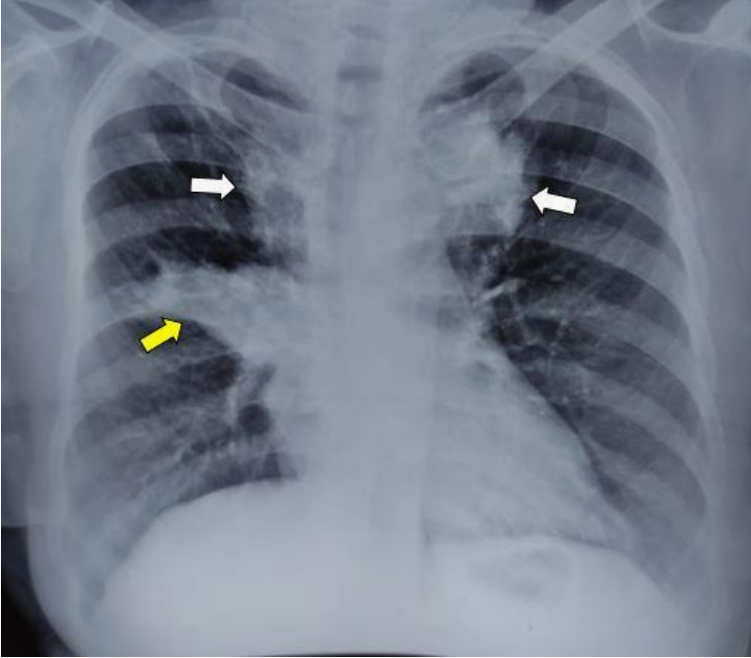

胸片:显示不均匀的放射性阴影,累及气管旁两侧上部区域,呈V形。右肺门增大,右肺门旁可见类似的放射性阴影,主要累及右肺中叶,显示典型的手套指征(图1)。

图1 不均匀的放射性阴影(白色箭头),累及气管旁两侧上部区域,呈V形,右肺门增大,右肺门旁可见类似的放射性阴影(黄色箭头)